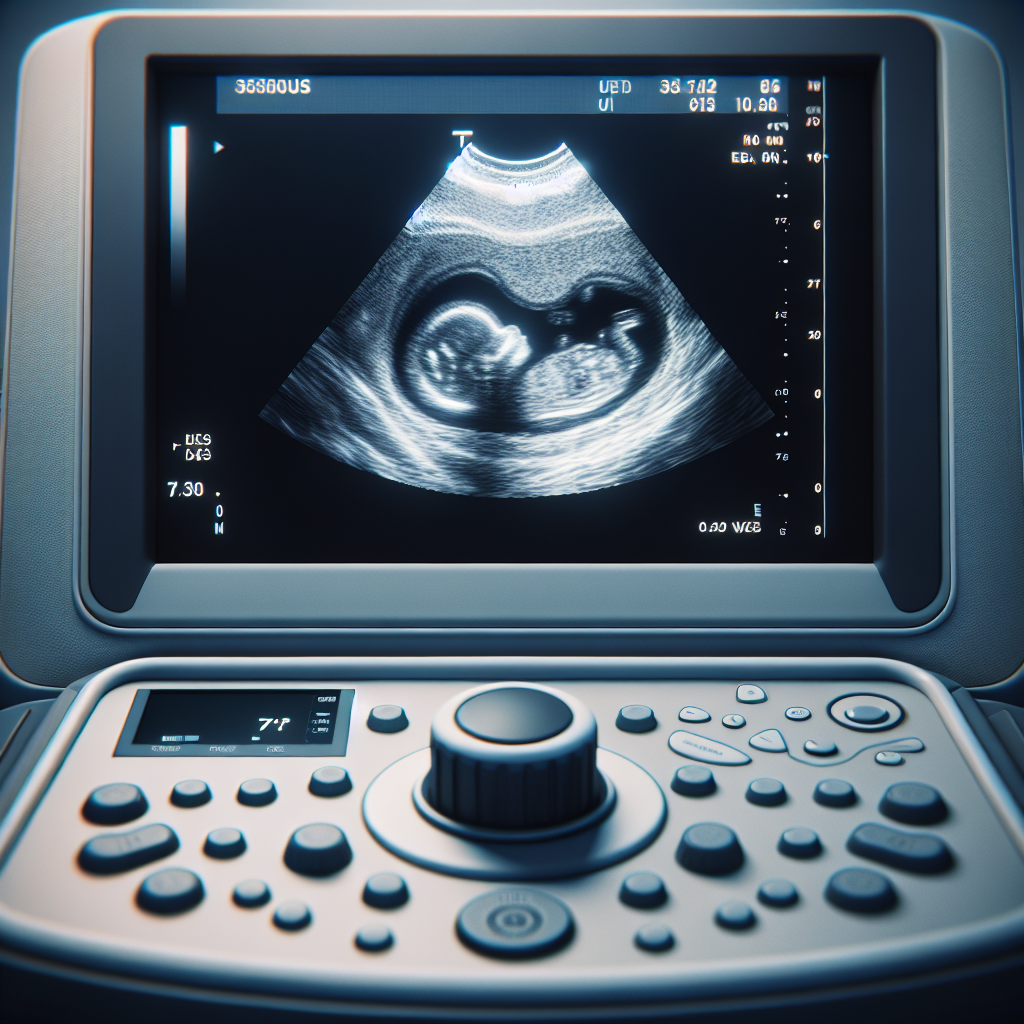

An obstetric ultrasound, often simply called a prenatal ultrasound, uses high-frequency sound waves to create live images of your baby inside the womb. These sound waves are completely harmless to both you and your baby, making it an incredibly safe procedure. The images, visible on a screen, allow our medical team to observe your baby’s growth, development, and overall health.

Far beyond just seeing your baby, an obstetric ultrasound provides critical medical information. It helps confirm your pregnancy, accurately date it, and determine if you are carrying more than one baby. As your pregnancy progresses, it allows for detailed assessment of organ development, detection of potential anomalies, monitoring of amniotic fluid levels, and evaluation of the placenta’s health and position. This detailed health check is vital for proactive planning and intervention if needed.